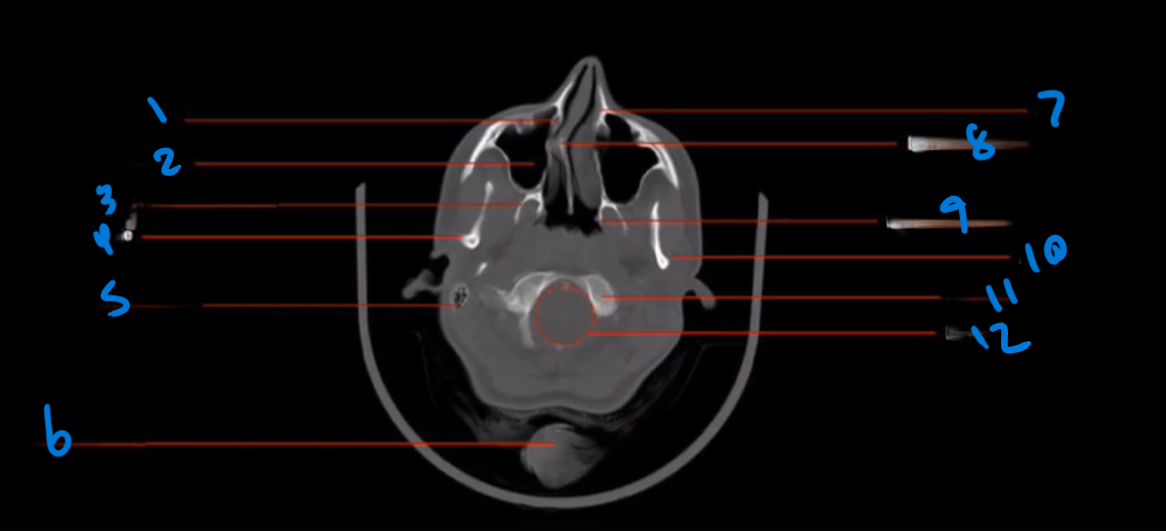

Landmark 1?

Maxillary Bone

Landmark # 2

Maxillary sinus

Landmark #3?

Coronoid process, mandible

Landmark # 4 called?

Mandibular condyle

Landmark # 5?

Carotid Canal

Landmark # 6?

Jugular Foramen

Landmark # 7?

Nasal Septum

Landmark # 8

Nasolacrimal duct

Landmark # 9

Zygoma

Landmark # 10

Zygomatic arch

Landmark # 11?

Clivus

Landmark # 12

External Auditory Meatus

Landmark # 13

Mastoid Air Cells, Temporal Bone